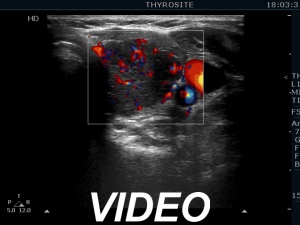

Second examination 19 months later (second row of images):

Comment. This is a typical presentation of a newly developed hypothyroidism regarding the change in echo pattern. Although the correlation between the echogenicity index and the hormonal status is week, in a particular patient, a developing hypothyroidism from an euthyroid state usually correlates with an increasing echogenicity index.Clinical data: This time the patient had no complaints, however the TSH was 16.8 mIU/L two month ago.

Palpation: no abnormality.

Laboratory tests: TSH 29.1 mIU/L, FT4 13.1 pM/L, aTPO 638 U/mL.

Ultrasonography. Compared with The previous examination, one change could be observed: the echogenicity index rose to 70-90%.

Daily 75 microgram levothyroxine was administered.